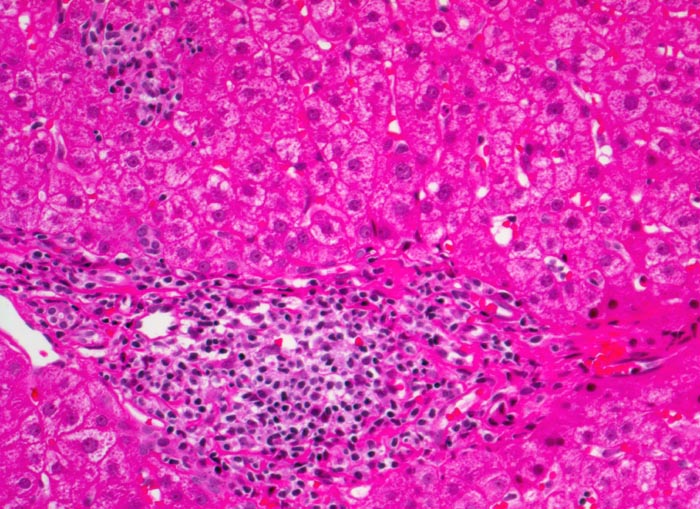

Morphologische Merkmale:

• Dichte mononukleäre portale und lobuläre Entzündungsinfiltrate mit Ausbildung von Lymphfollikeln in den Portalfeldern.

• Übergreifen der Entzündung auf das Parenchym (=Interface oder Grenzzonenhepatitis).

• Abgerundete hypereosinophile apoptotische Hepatozyten (Councilman-Körperchen).

• Geringe Portalfeldfibrose. Das sollte der Kliniker dem Pathologen mitteilen: